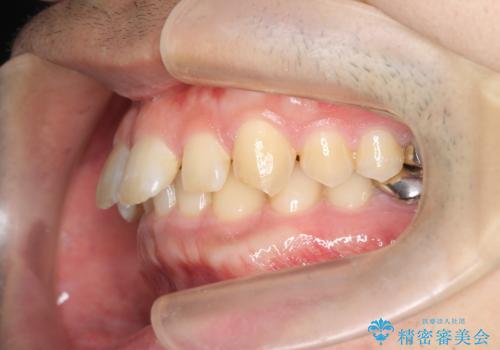

ディープバイトのマウスピース矯正

- 飛び出してしまい、隙間のある前歯をきれいに並べたい、と矯正治療を希望され来院されました。

上顎前歯を後方に引き、隙間を閉じるためには下顎前歯の絶対的な圧下を行い、深い噛み合わせを改善することが必要です。

圧下は歯の動きの中でも難しい動きの一つで時間がかかることが多いです。

前歯でチューイーをしっかり噛み、咬合圧を伝えたことで下顎前歯が圧下し、上顎前歯の隙間を閉じることができました。